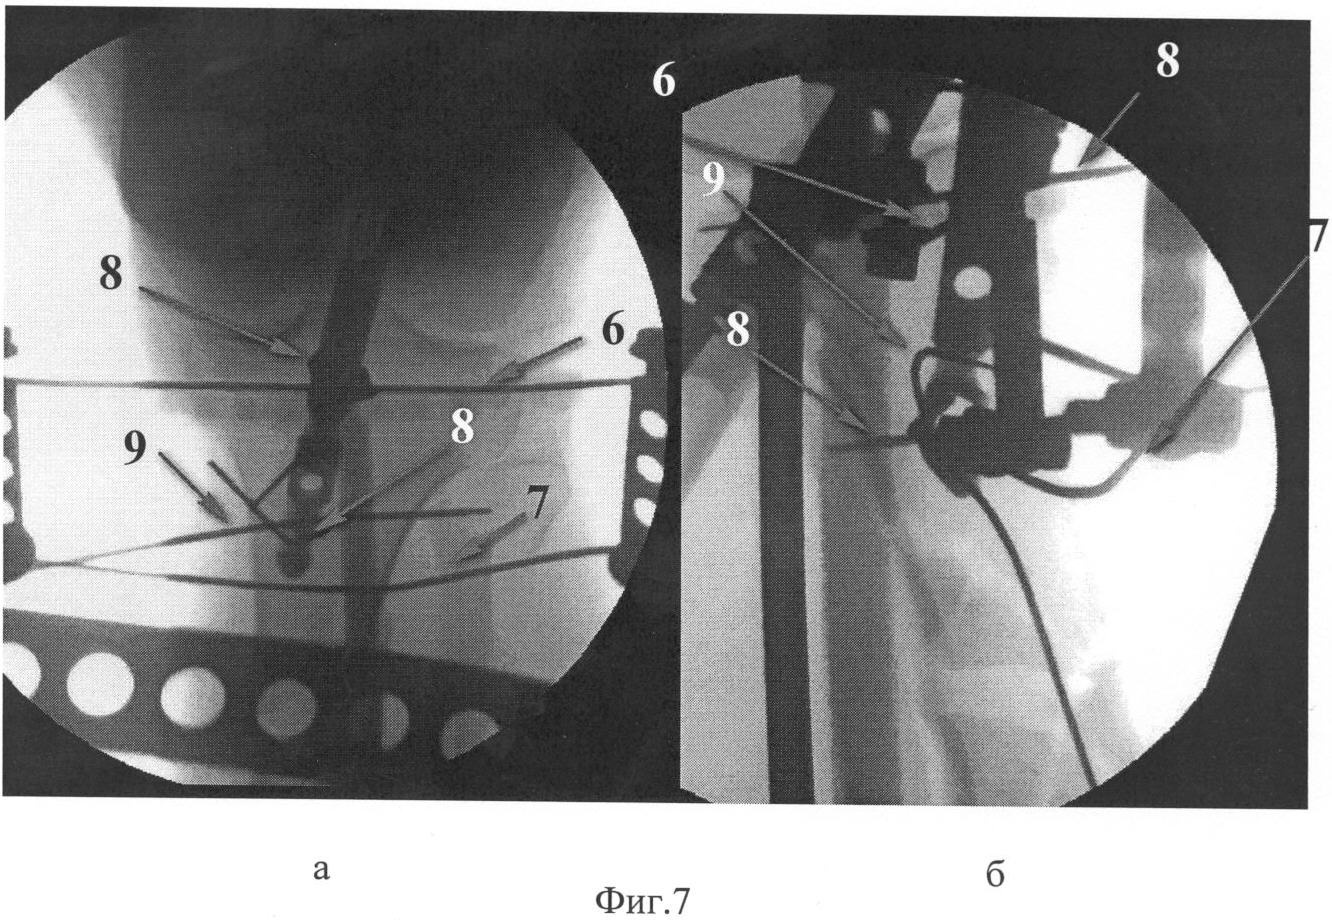

Для предотвращения типичного при введении гвоздя отклонения его кнаружи под рентгенологическим контролем проводят две отклоняющие спицы 8 спереди назад по середине поперечника большеберцовой кости. Первая проводится ближе к суставной поверхности, вторая – ближе к дистальному концу центрального отломка. Для предотвращения смещения под углом, открытым кзади, и смещения периферического отломка кзади по ширине проводится отклоняющая спица 9 во фронтальной плоскости по середине поперечника. Спицы проводятся до выхода из второй стенки костной трубки без выкола через мышцы и кожу на противоположной стороне. При введении интрамедуллярного гвоздя его направляют так, чтобы он прошел кнаружи от проксимальной и кнутри от дистальной передне-задних спиц и кпереди от фронтальной спицы, тем самым устраняется тенденция к вальгусу и антекурвации.

На Фиг.6 показан наложенный дистрактор с введенными отклоняющими спицами, согласно схеме на Фиг.4. На Фиг.7 – рентгенологическая картина с введенными отклоняющими спицами: а – вид спереди; б – вид сбоку.